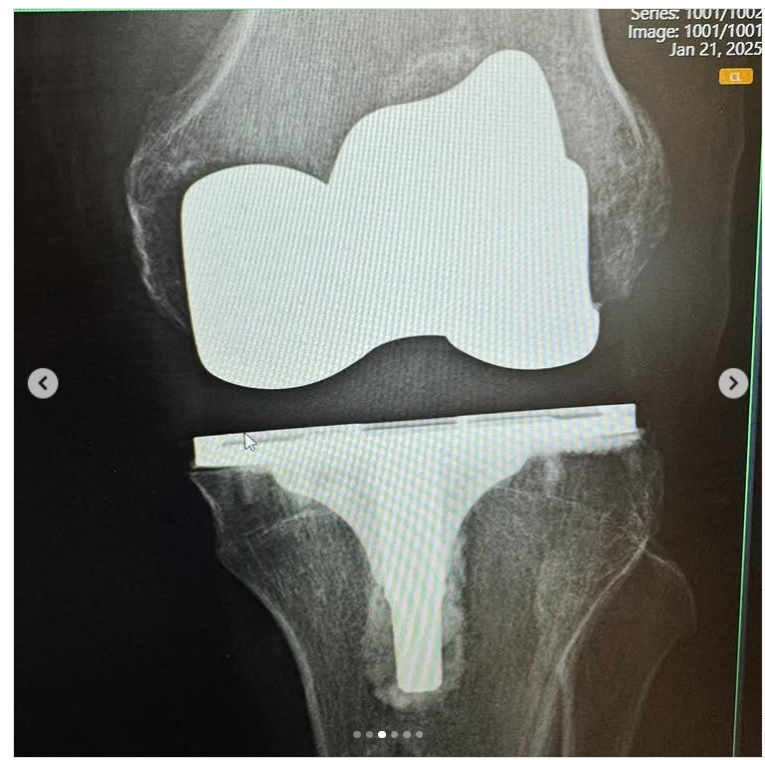

How it was. And how it is…

I am 7 weeks post op on a Total Knee Replacement. My left knee was on its last leg, and I have been putting this surgery off for years.

Post op X-Rays show everything is healing nicely.